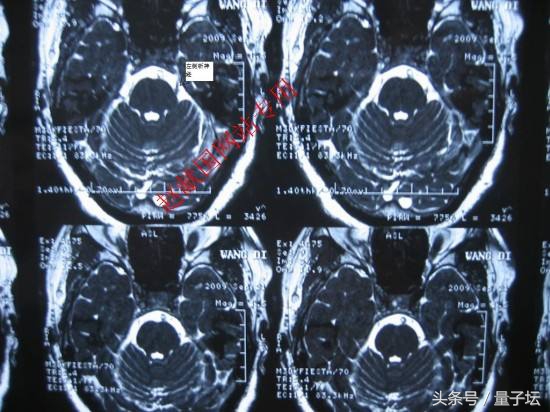

三叉神经痛是神经外科常见病之一,也是国际公认的疑难杂症之一。怎样治三叉神经痛,目前临床上存在的治疗三叉神经痛的方法有许多多种,这里将临床上常用的治疗三叉神经痛的方法向大家作简要的介绍:

4、手术治疗。可分为周围神经切断术,神经根切断术,三叉神经脊髓束切断术,三叉神经加压或减压术,三叉神经微血管减压术。以上方法都为破坏三叉神经,使三叉神经失去正常生理功能达到暂时止痛作用,可引起面神经麻痹、偏瘫、共济失调等后遗症,且一段时间后三叉神经重新再生,再次引起疼痛,复发率高。